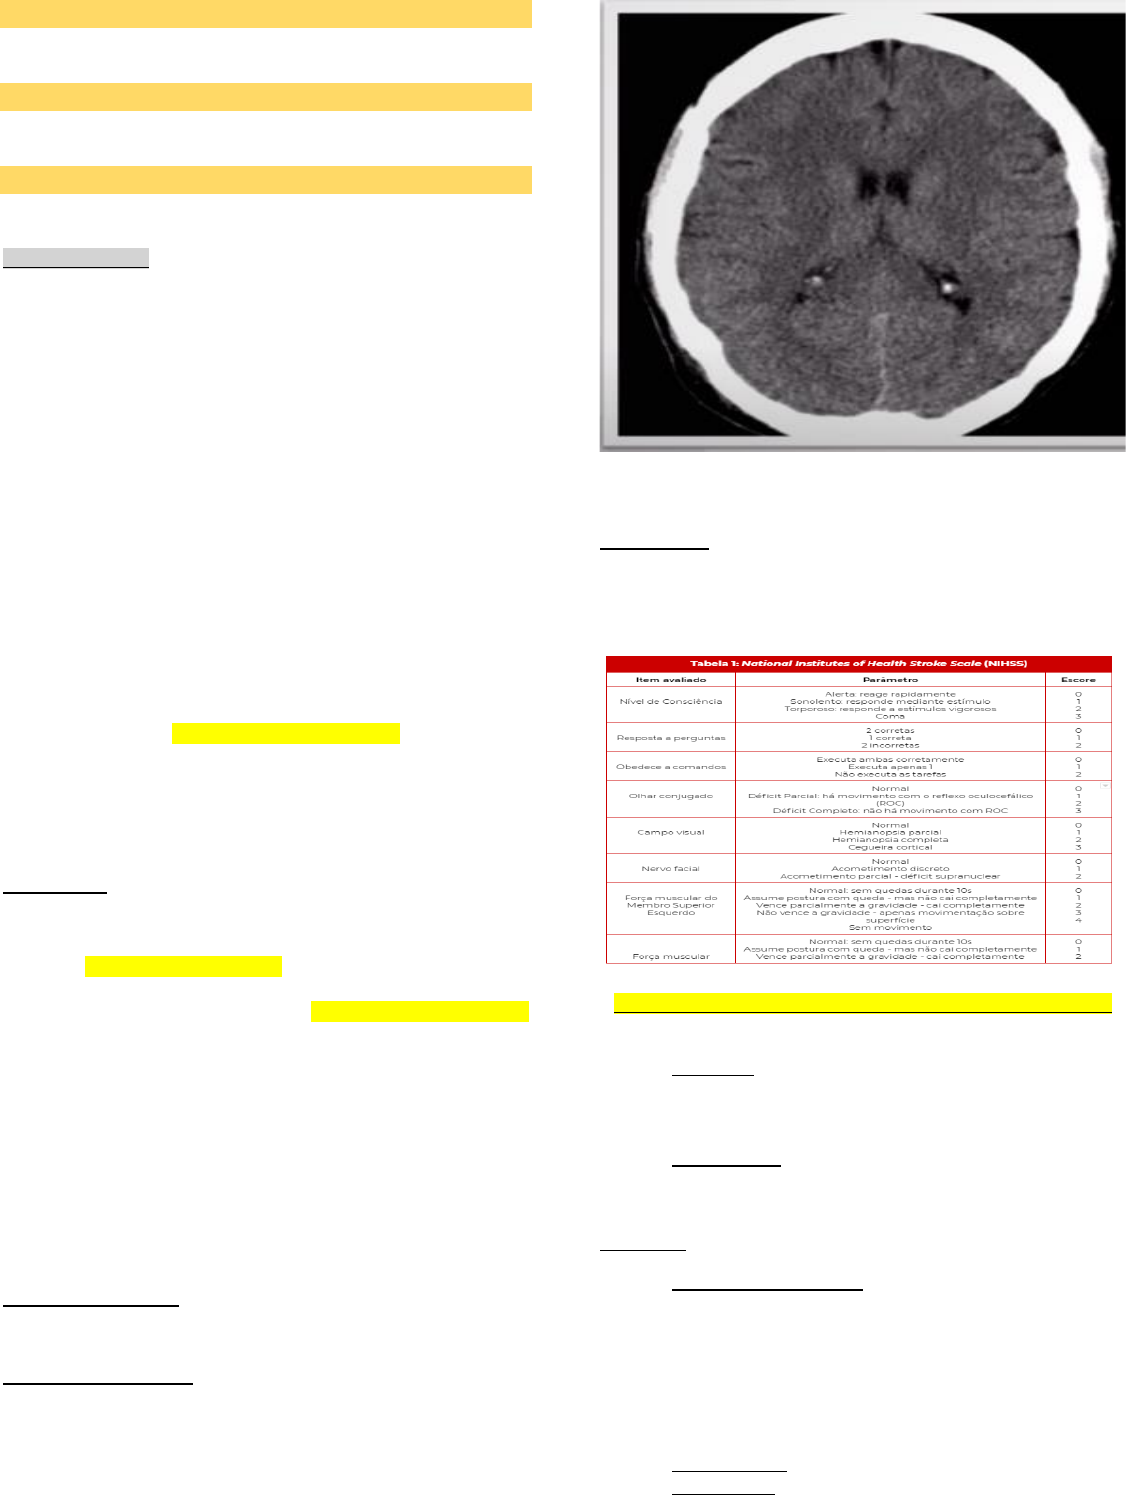

• TC até 20 minutos da admissão do paciente; Sem contraste ->

isso para diferenciar o isquêmico do hemorrágico, o isquêmico

pode vir normal. Não precisa da tomografia para confirmar, o

diagnóstico é clinico.

• TC ou RNM de crânio sem contraste (geralmente TC).

Ausência de hemorragia confirma isquemia. Imagem de

hipodensidade surge em 24 – 72 horas.

• Serve para diferenciar em isquêmico ou hemorrágico.

Tomografia de Crânio